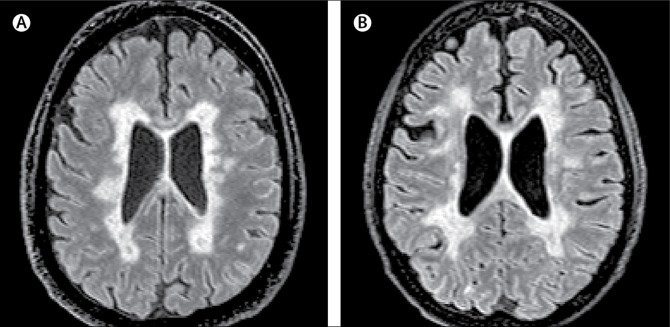

Vísindamenn greina nýtt afbrigði af MS

Vísindamenn hafa greint nýtt afbrigði af MS, MCMS, sem ekki sést á sneiðmynd af heila MS-sjúklings í MRI (segulómun), og því aðeins hægt að greina eftir andlát. Við MCMS eiga taugaskemmdir sér stað án niðurbrots á mýelíni í heila, eins og talið er einkennandi fyrir MS-sjúkdóminn.